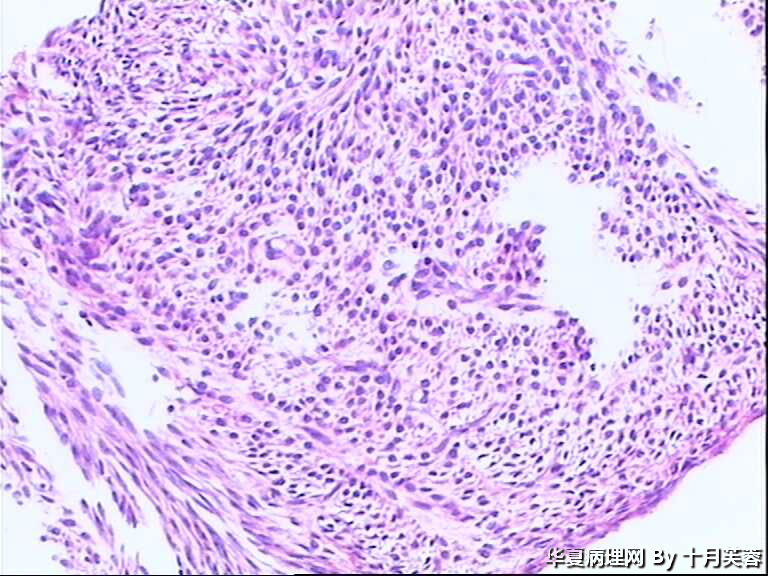

女性,50岁,临床申请单“子宫肌瘤穿刺”

平滑肌瘤?间质肿瘤?

具体到这一例,感觉要是子宫肌瘤的话则问题不大。但若是GIST,PECOMA,SFT等则不好说了!